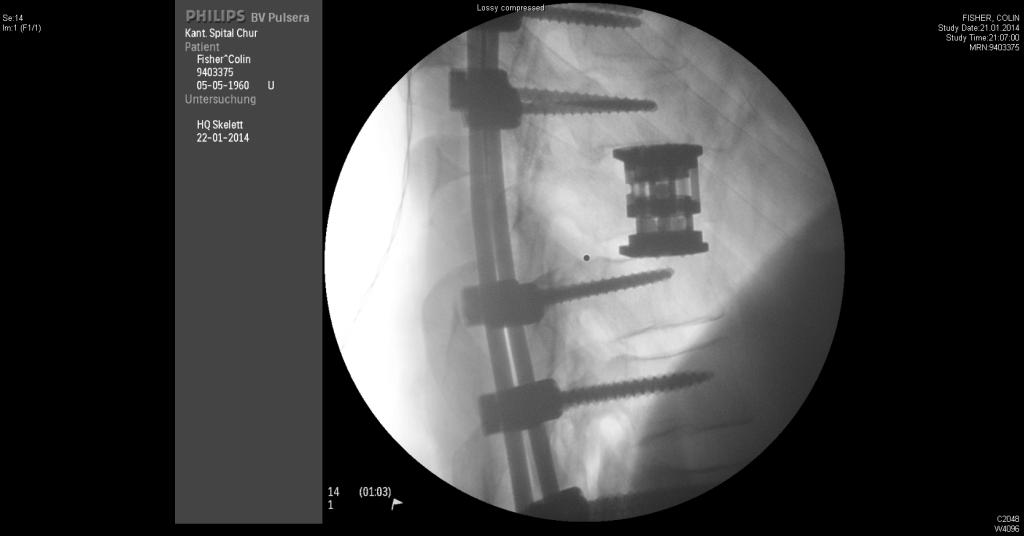

At the hospital a young doctor showed me my x-ray. The shock wave down my spine had destroyed my T-9 vertebra and split the T-11. He had consent forms for an emergency operation. I signed. I woke up the next morning in intensive care after a 6 hour operation to replace my vertebra with a titanium cage and titanium poles down my spine to support me for the rest of my life.